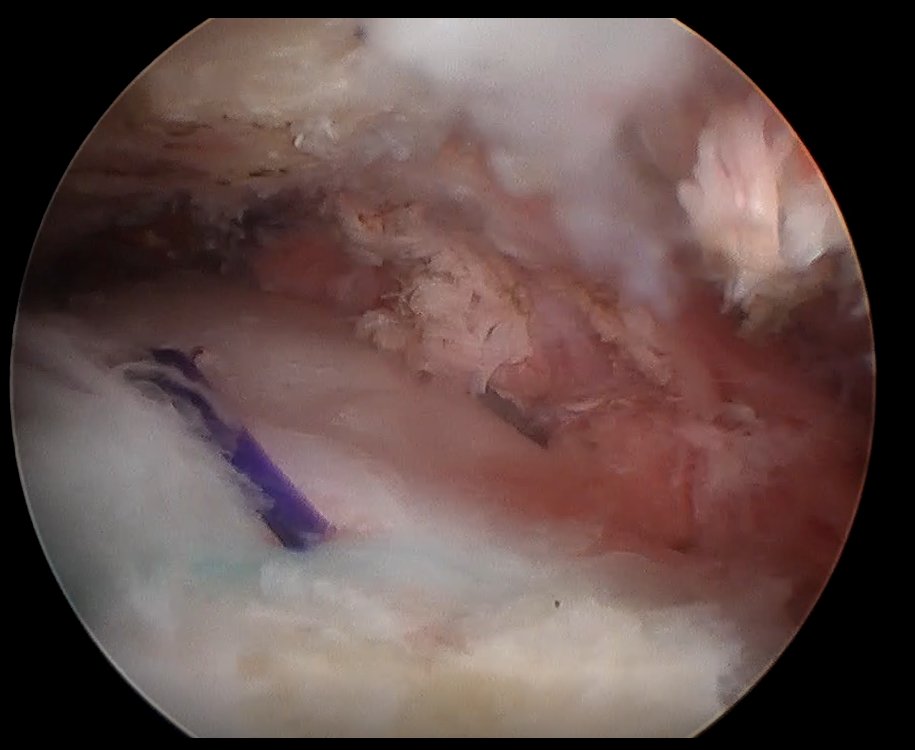

حقق قسم جراحة العظام في مستشفى المانع فرع الخبر إنجازًا طبيًا لافتًا، بقيادة الدكتور محمد المجتبى بعد أن تمكن مريض يبلغ من العمر 61 عامًا من استعادة كامل مدى الحركة في كتفه خلال أربعة أسابيع فقط من خضوعه لعملية إصلاح الأوتار بالمنظار باستخدام رقعة الكولاجين التعويضية، وهي تقنية طبية حديثة تُستخدم لتعزيز التئام الأوتار وتسريع عملية التعافي.